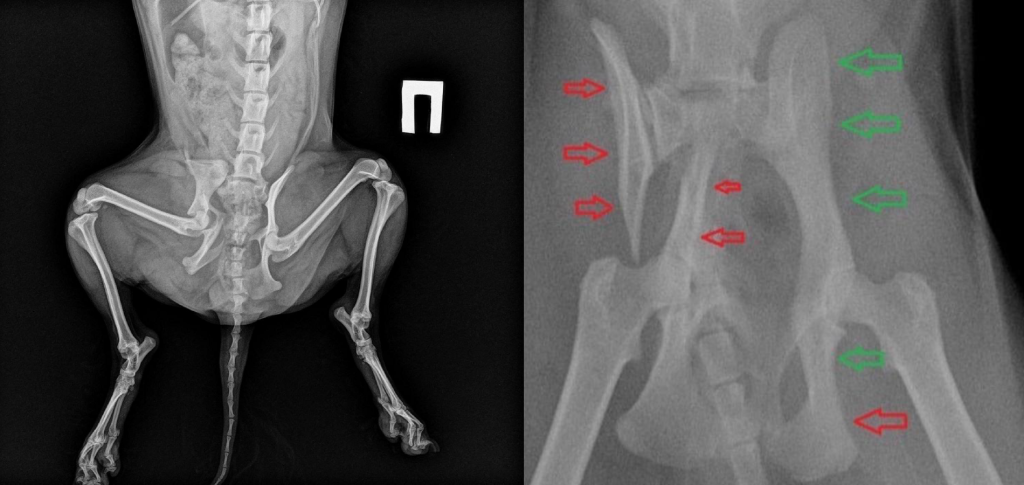

(Переломы таза и челюсти у собак после автотравмы)